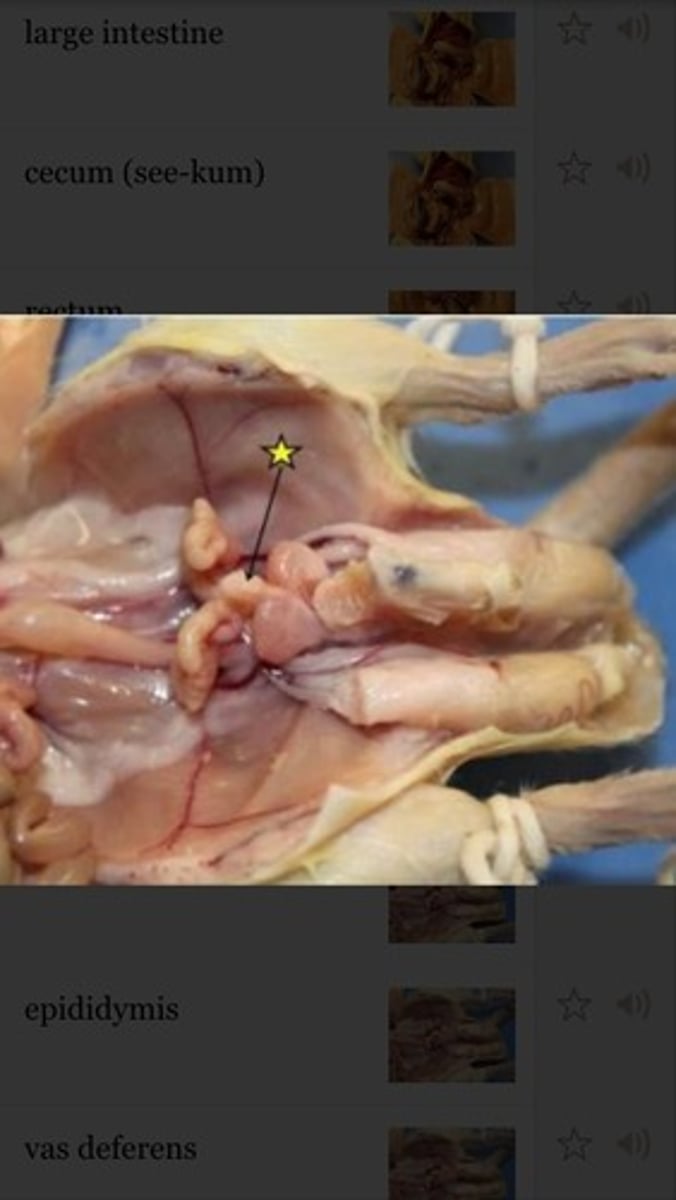

large intestine

cecum

Specific

cecum